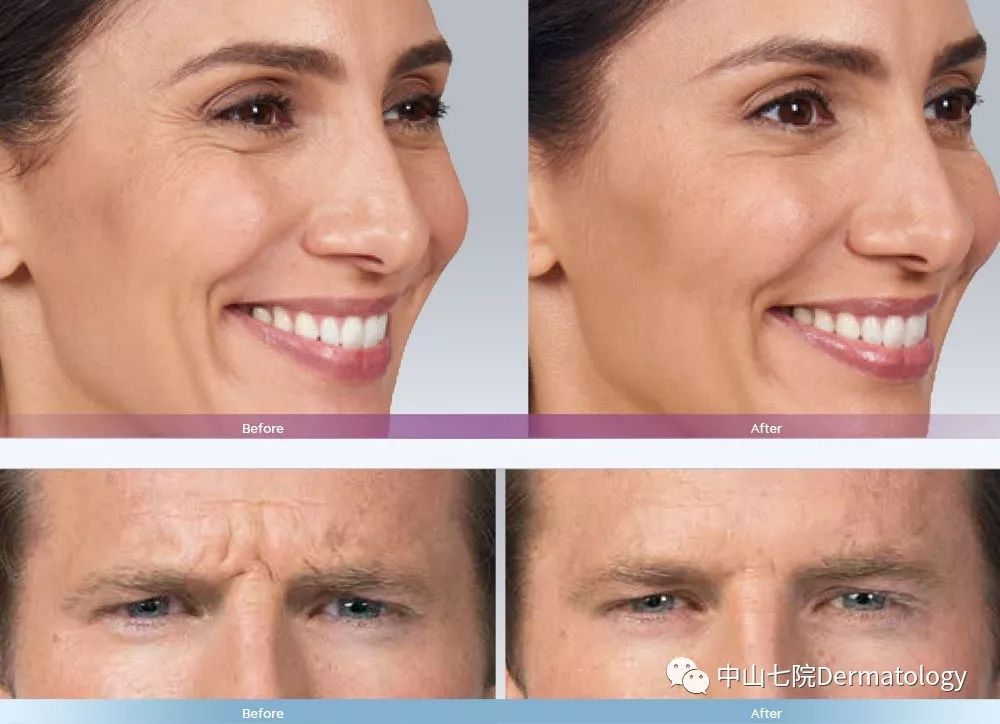

(1)除皱:注意咯!!肉毒素虽然全身魔力加持,但也不是所有皱纹都可以去除的。伴随我们面部表情肌肉收缩所产生的皱纹(如鱼尾纹,眉间纹,额纹),我们称之为动态皱纹。肉毒素仅对这些皱纹疗效显著。

(2)轮廓塑性:以瘦脸为例,一部分人群脸大主要是因为咬肌肥大,肉毒素通过选择性萎缩部分肌肉从而让你瘦脸不是梦!!瘦腿瘦肩是一个道理,只是作用于不同的肌肉。

除皱—抚平岁月痕迹

瘦脸